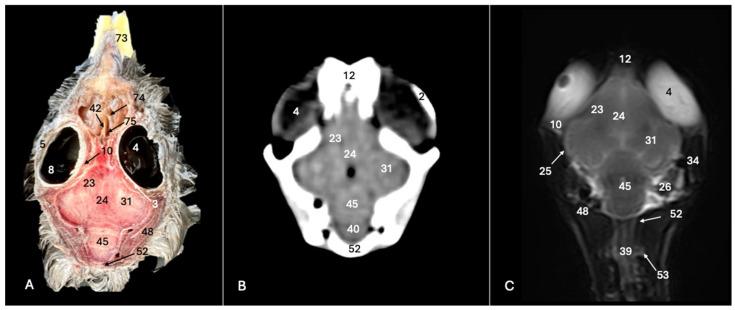

科里氏剪水鹱(:通过横断面解剖、计算机断层扫描和磁共振成像探索正常头部解剖结构。

Cory's Shearwater (): Exploring Normal Head Anatomy through Cross-Sectional Anatomy, Computed Tomography and Magnetic Resonance Imaging.

Cory's shearwater, or , stands out as a symbolic figure in the world of seabirds, playing a crucial role in marine ecosystems globally. Belonging to the Procellariidae family, it is singularized by its imposing wingspan and intricate migration patterns connecting it to various regions from the North Atlantic to the Pacific. Its role in the marine food chain, specialized diet and adaptation for nesting in the Canary Archipelago underscore its ecological importance. However, Cory's shearwater also faces important threats, such as the invasion of foreign species, highlighting the need for its conservation. Among the conservation issues, studies on its biology, the main threats it faces and its normal anatomy are essential to preserve marine biodiversity. Additionally, a variety of imaging techniques, such as computed tomography and magnetic resonance, facilitates the understanding of the bird's neuroanatomy and opens future research possibilities in comparative neuroscience. Moreover, this approach proves particularly relevant given the increasing attention these seabirds receive in environments such as zoos, rehabilitation centers and their natural habitat, where veterinarians play a crucial role in their care and well-being.

摘要

科里氏剪水鹱,或称[具体名称],在海鸟世界中是一个具有象征意义的物种,在全球海洋生态系统中发挥着关键作用。它属于鹱科,其显著特征是翼展巨大,以及有着复杂的迁徙模式,使其与从北大西洋到太平洋的各个地区相连。它在海洋食物链中的作用、特殊的饮食习性以及在加那利群岛筑巢的适应性,都凸显了其生态重要性。然而,科里氏剪水鹱也面临着重大威胁,比如外来物种的入侵,这凸显了对其进行保护的必要性。在保护问题中,对其生物学、面临的主要威胁以及正常解剖结构的研究对于保护海洋生物多样性至关重要。此外,诸如计算机断层扫描和磁共振等多种成像技术,有助于了解该鸟类的神经解剖结构,并为比较神经科学开启未来的研究可能性。而且,鉴于这些海鸟在动物园、康复中心及其自然栖息地等环境中受到越来越多的关注,这种方法被证明尤为重要,在这些环境中,兽医在它们的护理和健康方面发挥着关键作用。